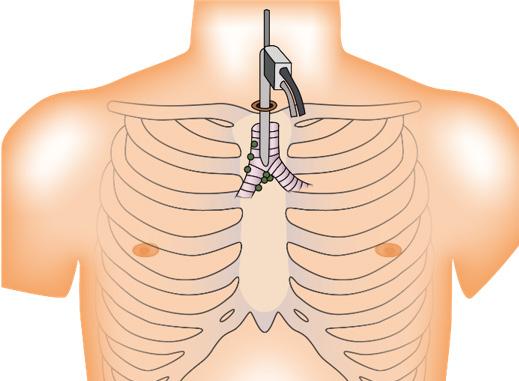

Tratamiento

Toracostomía / drenaje torácico con tubo torácico de 28 a 32 French (Toracotomía mínima cerrada) → a nivel del quinto espacio intercostal con la línea axilar anterior o media (triangulo de seguridad)

Figura 13. Toracostomía → colocación de tubo de drenaje torácico Figura 14. Toracotomía abierta

Se utiliza un tubo torácico francés de tamaño 28 a 32 Fr con sello de agua o succión (presión negativa de -20 a -25 cmH 2 O) → a nivel del quinto espacio intercostal con la línea axilar anterior o media (triangulo de seguridad)

El triángulo de seguridad es un término que se utiliza para describir los puntos de referencia anatómicos utilizados durante la inserción del drenaje torácico. La axila forma el ápice y el triángulo está formado por el borde lateral del pectoral mayor y el borde lateral del dorsal ancho